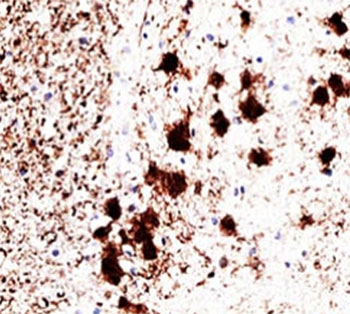

PGP9.5 Antibody Clone 31A3 for IHC. Immunohistochemistry analysis of PGP9.5 / UCHL1 in human brain tissue. Formalin-fixed, paraffin-embedded human brain tissue stained with PGP9.5 Antibody for IHC, also known as UCHL1 antibody or Ubiquitin C-terminal hydrolase L1 antibody, demonstrates strong cytoplasmic and neuritic HRP-DAB brown staining in neuronal cells, with clear labeling of neuronal cell bodies and processes while surrounding non-neuronal cells show minimal signal. Clone 31A3 antibody shows a well-defined neuronal staining pattern consistent with published observations, supporting its use as a widely cited and trusted reagent for detecting UCHL1 expression in neural tissue. Antigen retrieval was performed by heating sections in pH 9 Tris-EDTA buffer at 95oC for 45 minutes followed by cooling at room temperature for 20 minutes.